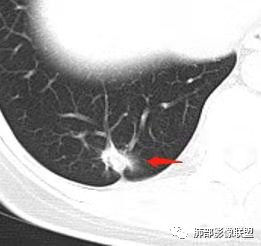

右肺下叶实性病灶,边缘可见月牙铲 胸膜牵拉  棘突征,增强可见强化,考虑恶,浸润腺癌?

确实是GGO,边界清,考虑腺癌如果不是,则是炎症

二.右肺下叶病灶

右肺下叶胸膜下结节判断难度较大。

病灶边缘以收缩为主,长大棘状突起,胸膜牵拉凹陷明显,说明病灶纤维化明显,倾向炎症或腺癌,但病灶GGO模糊,且未见异常强化,按理考虑慢性炎性可能较大。可以穿刺活检除外腺癌可能。粘液腺癌很少有如此显著的牵拉能力。